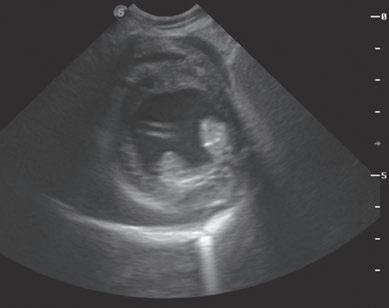

La responsabilidad de los artículos, reportajes, comunicados, etc. recae exclusivamente sobre sus autores. El editor sólo se responsabiliza de sus artículos o editoriales. La ciencia veterinaria está sometida a constantes cambios. Así pues es responsabilidad ineludible del veterinario clínico, basándose en su experiencia profesional, el correcto diagnóstico de los problemas y su tratamiento. Ni el editor, ni los autores asumen responsabilidad alguna por los daños y perjuicios, que pudieran generarse, cualquiera que sea su naturaleza, como consecuencia del uso de los datos e información contenidos en esta revista. De acuerdo con la normativa vigente en materia de protección de datos Grupo Asís Biomedia, SL., es responsable del tratamiento de sus datos personales con la finalidad de enviarle comunicaciones postales de nuestras revistas especializadas, así como otras comunicaciones comerciales o informativas relativas a nuestras actividades, publicaciones y servicios, o de terceros que puedan resultar de su interés en base a su consentimiento. Para ello, Grupo Asís podrá ceder sus datos a terceros proveedores de servicios de mensajería. Podrá revocar su consentimiento, así como ejercer sus derechos de acceso, rectificación, supresión, oposición, limitación y portabilidad enviando un correo electrónico a protecciondatos@grupoasis.com, o una comunicación escrita a Grupo Asís en Centro Empresarial El Trovador, planta 8, oficina I, Plaza Antonio Beltrán Martínez 1, 50002, Zaragoza (España), aportando fotocopia de su DNI o documento identificativo sustitutorio e identificándose como suscriptor de la revista. Asimismo, si considera que sus datos han sido tratados de forma inadecuada,